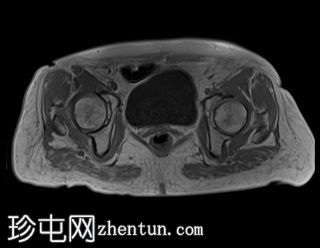

轴位

DWI

中下段直肠肿块,形态不规则,边缘清晰,质地不均一,以囊性为主,多分叶,增强扫描时实性部分强化,弥散不受限,病灶下缘位于肛门直肠连接处30毫米处,呈半圆形,横跨半径3点至9点方向,纵轴长约44毫米,向直肠系膜脂肪方向延伸达15毫米,但未超过直肠系膜筋膜。直肠上段无改变。未观察到淋巴结肿大。